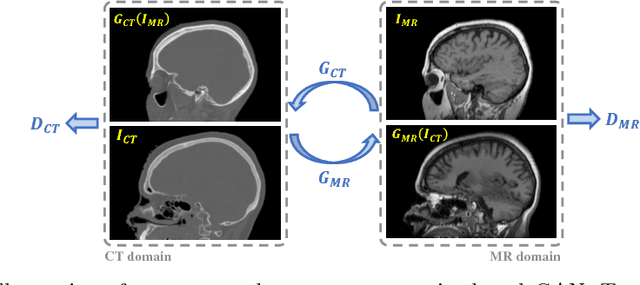

Abstract:The cycleGAN is becoming an influential method in medical image synthesis. However, due to a lack of direct constraints between input and synthetic images, the cycleGAN cannot guarantee structural consistency between these two images, and such consistency is of extreme importance in medical imaging. To overcome this, we propose a structure-constrained cycleGAN for brain MR-to-CT synthesis using unpaired data that defines an extra structure-consistency loss based on the modality independent neighborhood descriptor to constrain structural consistency. Additionally, we use a position-based selection strategy for selecting training images instead of a completely random selection scheme. Experimental results on synthesizing CT images from brain MR images demonstrate that our method is better than the conventional cycleGAN and approximates the cycleGAN trained with paired data.